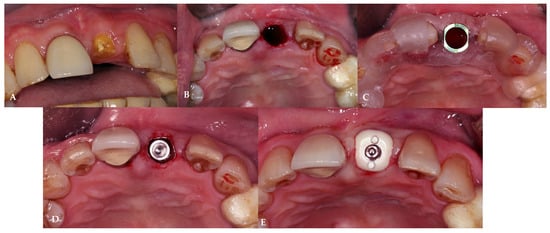

2.7. Case Presentation